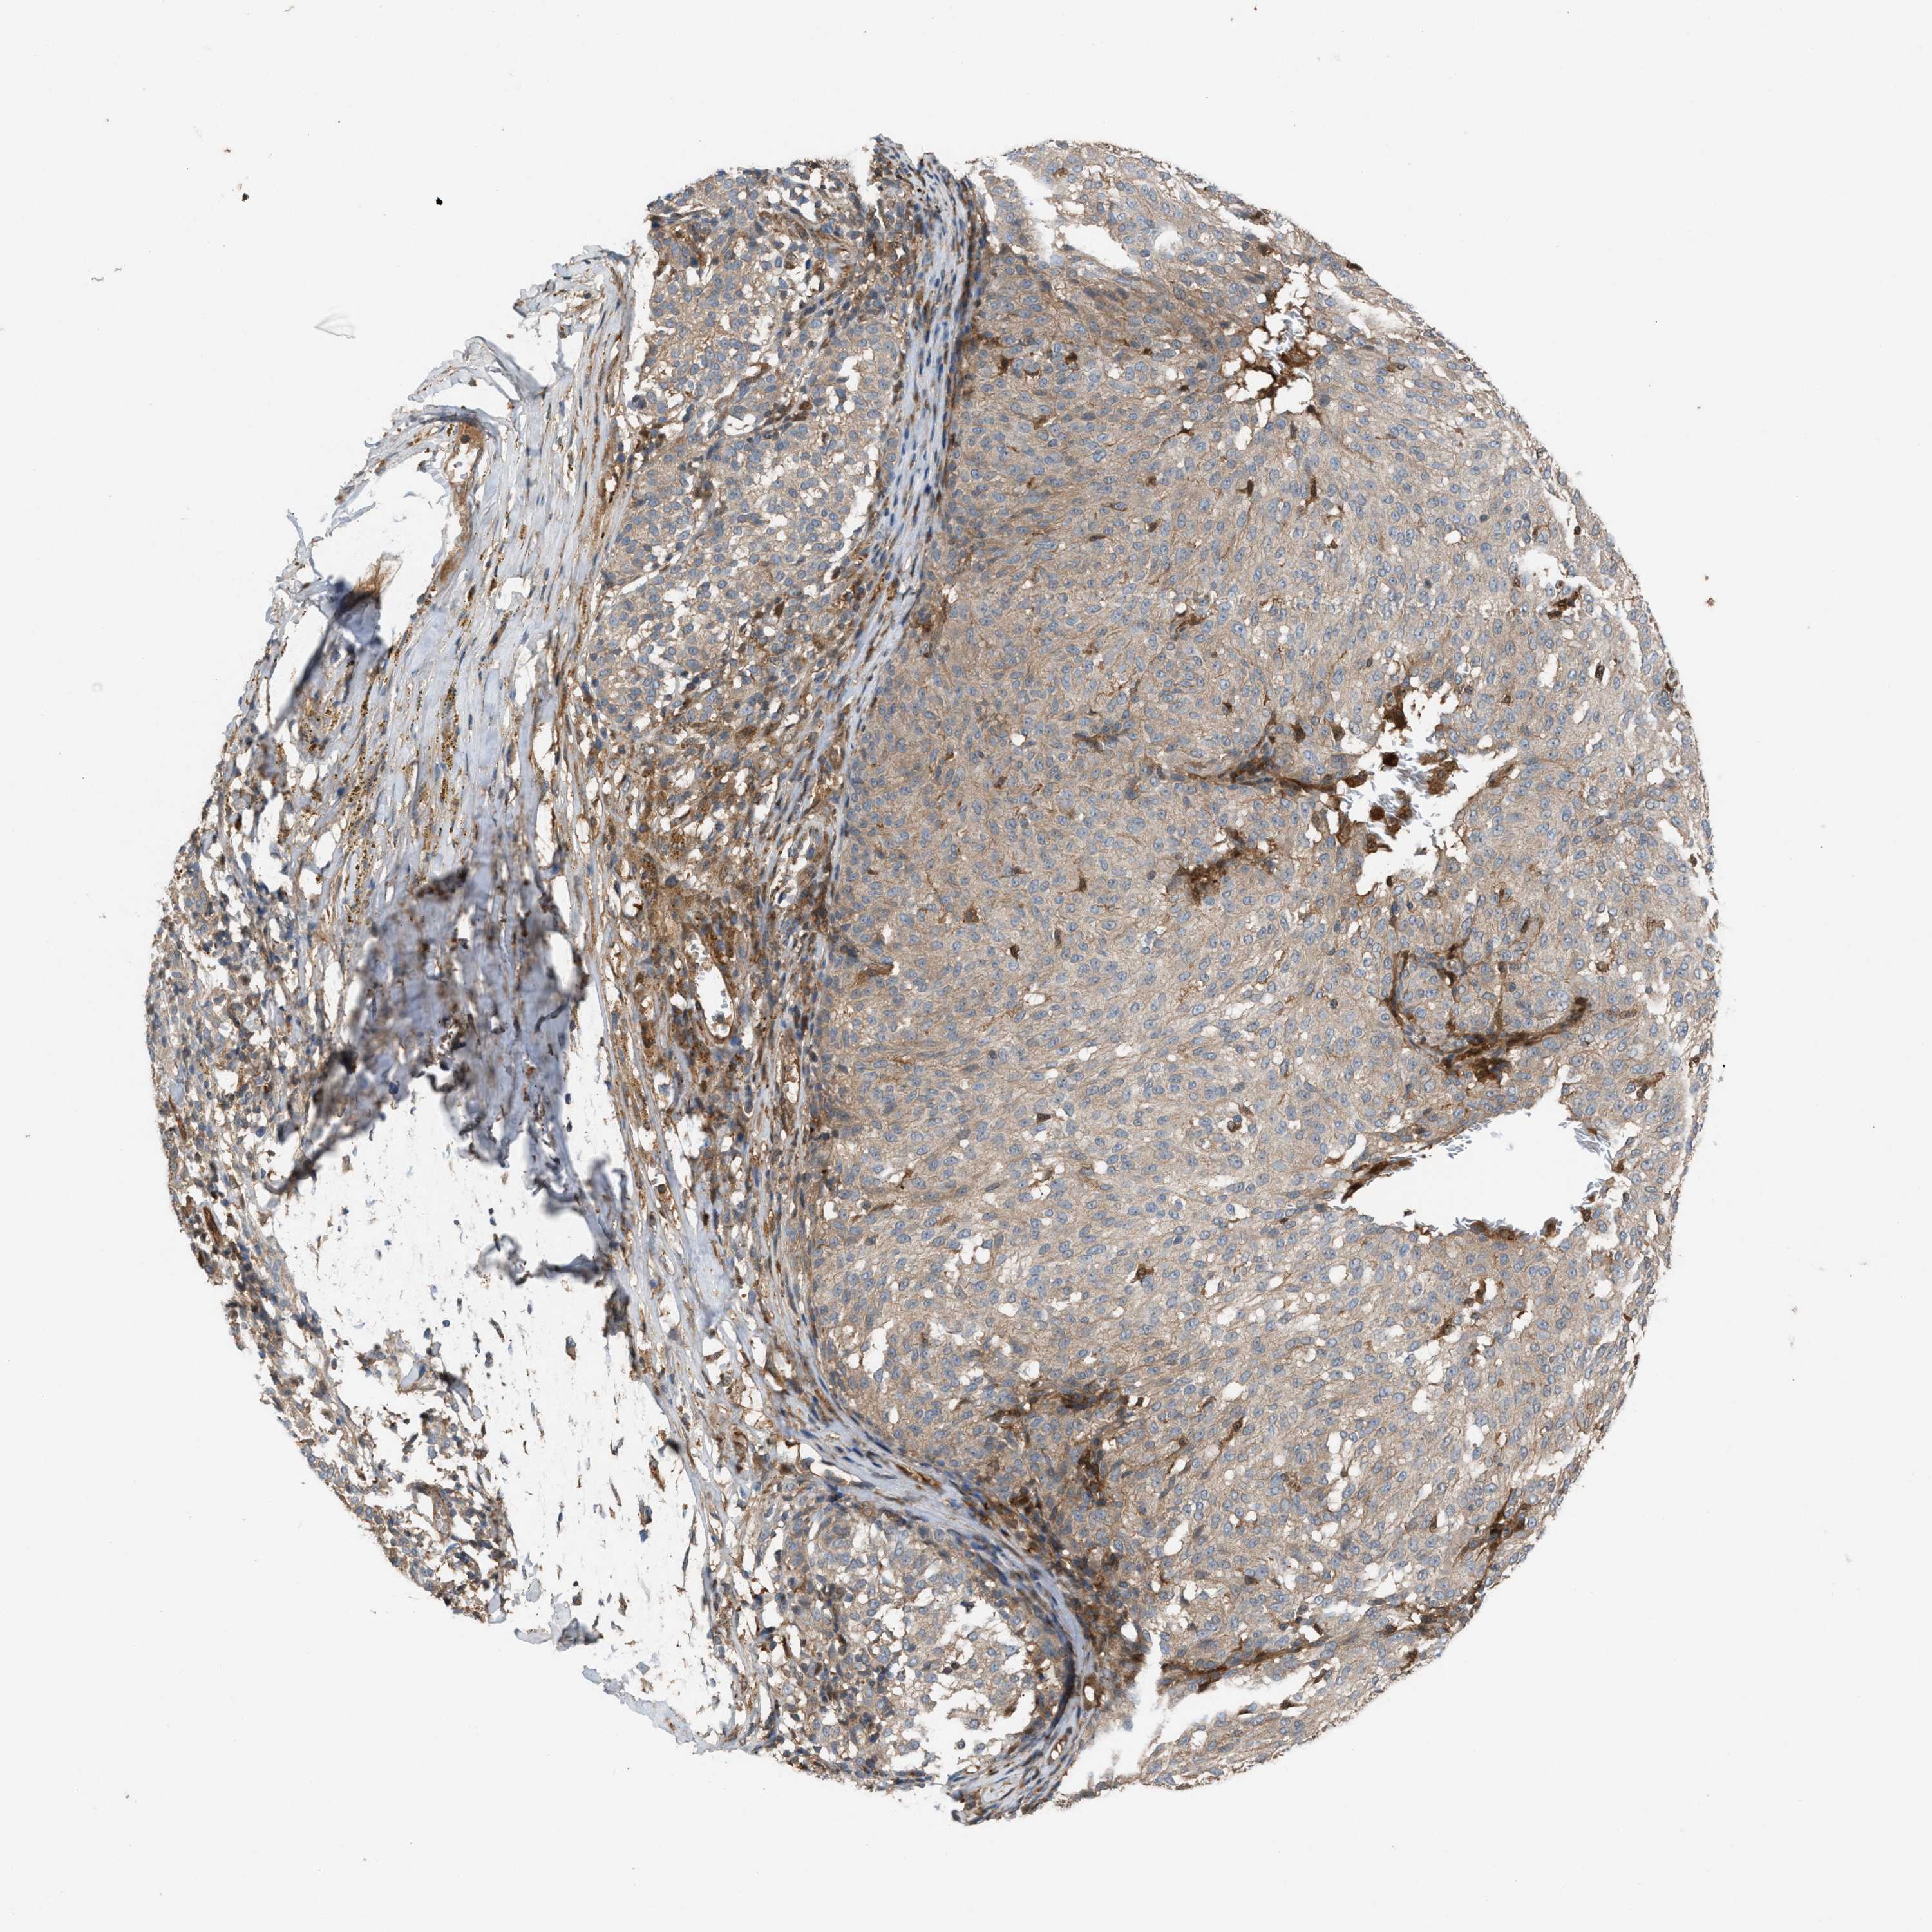

MELANOMA - Protein expressioni

A mouse-over function shows sample information and annotation data. Click on an image to view it in a full screen mode. Samples can be filtered based on level of antibody staining by selecting one or several of the following categories: high, medium, low and not detected. The assay and annotation is described here.

Note that samples used for immunohistochemistry by the Human Protein Atlas do not correspond to samples in the TCGA dataset.

Antibody stainingi

Antibody staining in the annotated cell types in the current human tissue is reported as not detected, low, medium, or high, based on conventional immunohistochemistry profiling in selected tissues. This score is based on the combination of the staining intensity and fraction of stained cells.

Each image is clickable and will lead to virtual microscopy that enables deeper exploration of all samples and also displays staining intensity scores, fraction scores and subcellular localization as well as patient and tissue information for each sample.

Antibody HPA021545

Antibody HPA021849

Staining

High

Medium

Low

Not detected

Intensity

Strong

Moderate

Weak

Negative

Quantity

>75%

75%-25%

<25%

None

Location

Nuclear

Cytoplasmic/membranous

Cytoplasmic/membranous,nuclear

Malignant melanoma, NOS

Malignant melanoma, Metastatic site